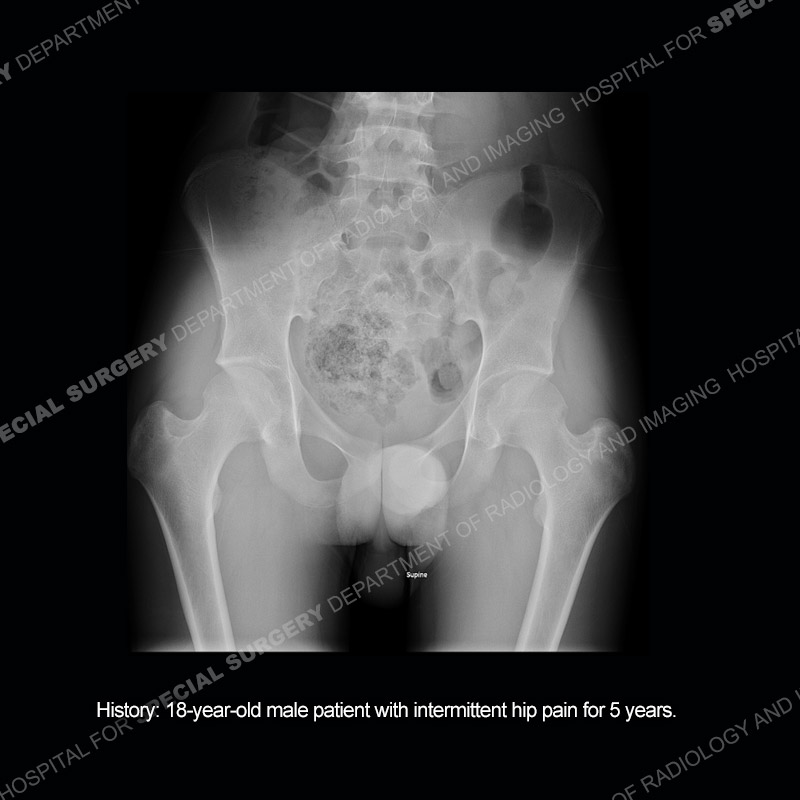

Case 213: 8-year-old male patient with intermittent hip pain for 5 years.